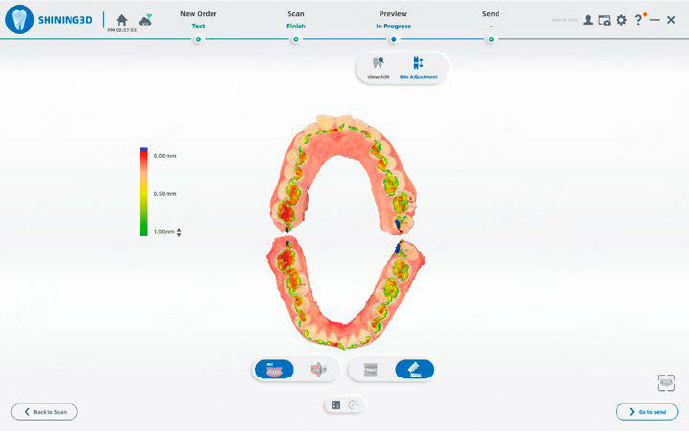

RILEVAMENTO DEI CONTATTI OCCLUSALI

Visualizzazione intuitiva dei contatti tramite mappa cromatica e vista sezionale, per valutare in modo efficiente le relazioni occlusali.